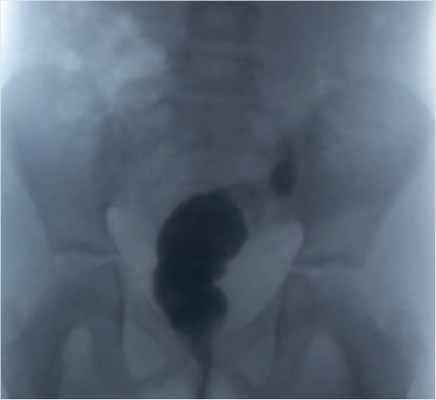

В рамках предоперацинного обследования выполнена ирригография: per rectum с помощью шприца введено 200 мл бариевой взвеси. Толстая кишка выполнена до нисходящих отделов, расположена обычно. «Неоампула» сформирована достаточно, не расширена, контуры четкие, неровные. Аноректальный угол удовлетворительный. Позыв на акт дефекации после введения 100 мл контрастного вещества. Опорожнение полное (рис. 7).

Рисунок 7. Ирригография при катамнестическом обследовании через 6 мес. после операции